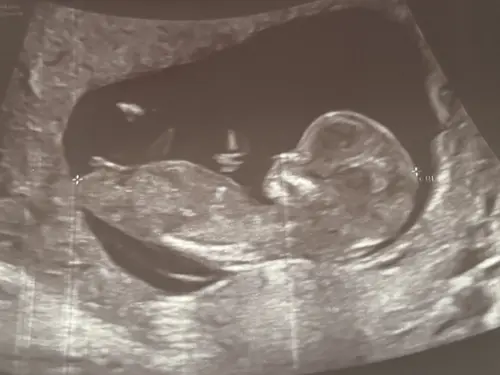

Hier is geen nub uit te halen of wel? Ik zit door al mijn foto's te kijken van de 13 weken echo maar ik kan niet echt een nub vinden, maar dat kan ook mijn eigen incompetentie hierin zijn hahaha

Nee hier zit het been voor. Als je er meer hebt kan je ze plaatsen ☺️

Echo van 12+6 maar ik geloof dat onze eigenwijze draaikont de beentjes in de weg legt 😅😅 de hele echo was uberhaupt 1 grote uitdaging dus de andere foto's zijn niet beter

Sorry geen nub te zien